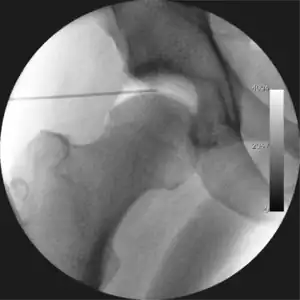

Intraoperative fluoroscopic image during an arthroscopic resection of a cam lesion of the femur. The upper instrument is the arthroscope (viewing device), while the lower is the high-speed burr used for reshaping the bone.

The procedure is performed with the patient asleep (general anaesthetic) or under spinal anaesthesia. There are two widely used methods, one with the patient on their back (supine) and the other on their side (lateral decubitus). Which is used is down to the surgeon's preference. To gain access to the central compartment of the hip joint (between the ball and socket), traction is applied to the affected leg after placing the foot into a special boot. (See fig. 2) There is specifically designed equipment for this, although some surgeons use a 'traction table', initially designed to help in the operative fixation of broken thigh and lower leg bones. The amount of traction (or pull) needed is assessed with the help of fluoroscopy (low-dose portable x-ray). (See fig. 3) It is usually not possible to distract the ball from the socket with traction alone by more than a few millimetres. Once the surgeon is happy that they will be able to gain access to the hip joint (i.e. the ball will distract from the socket by a small amount), the patient is then painted with antiseptic and the surgical drapes applied.

The next step is to insert a fine needle under x-ray guidance into the hip joint. This breaks the 'suction seal' of the joint and allows further distraction if necessary (see fig 4). The surgeon wishes to see the ball move out the socket by approximately 1 cm, so that access to the hip joint can be achieved with minimal risk of damage to the joint surfaces. Most surgeons will inject fluid into the joint at this stage, again to ensure that there is enough space between the ball and socket for safe instrument access. This needle is then removed. The next step is placement of the 'portals', or the small holes made to pass instruments into the joint. This is achieved by again passing a fresh hollow needle into the joint under x-ray control, usually in a slightly different position. The reason for this is so the surgeon can ensure that the needle, and subsequent cannulae do not penetrate and damage the acetabular labrum or cartilage joint surfaces (see fig. 5). Again, surgeons will have their own preferences as to their preferred placement. Through this hollow needle, a long thin flexible guide wire is passed into the joint, and the needle is removed over it, leaving the guide wire in situ. A small cut in the skin is made around the wire, to allow for larger cannulae to be placed over the wire through the portal. The wire therefore guides the larger cannulae into the joint. The most common external diameters of cannulae used are between 4.5 and 5.5 mm. Once the surgeon is satisfied that the cannula is in the correct position, by a combination of feel and x-ray guidance, the guide wire can be withdrawn. Once the first portal is correctly placed, any further portals may be created once the camera is in position, to ensure that they are placed with minimal risk to the joint surfaces. This process can be repeated to gain as many points of entry to the hip joint as the surgeon requires, normally between two and four. Certain of these entry points will be used for the viewing arthroscope and others for operating instruments.

Standard arthroscopic treatment of symptomatic cam FAI involves debridement (resection) or repair of any labral [10] and chondral injuries [11] in the central compartment of the hip, and subsequent reshaping of the head-neck junction of the upper femur (osteochondroplasty) in the peripheral compartment [12][13] using high-speed motorised burrs that are similar in design to a dentist's drill (see fig. 9).